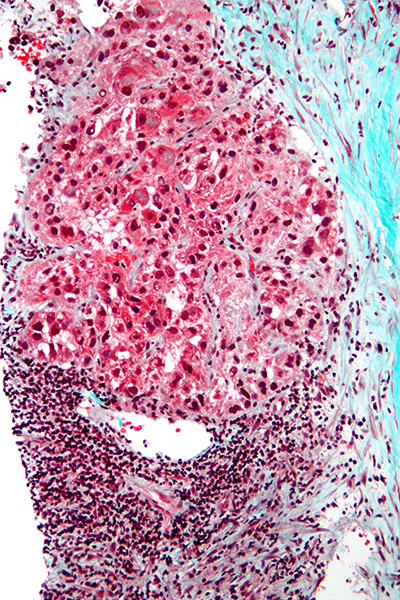

肝细胞癌 (图片来源:Wikipedia)